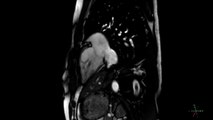

Savez-vous réaliser un massage cardiaque ? Quelles sont les étapes du massage cardiaque ? Tout ce qu'il faut savoir que la RCP (Réanimation Cardio-Pulmonaire).

00:20 Il réalise immédiatement une réanimation cardiopulmonaire.